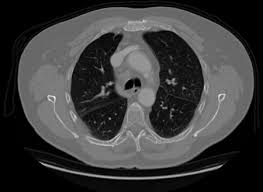

4) 진단 과정

CT, PET-CT, 조직검사 등을 통해 결절의 성격을 확인합니다. 영상 검사는 형태를 파악하는 데 유용합니다. 조직검사는 확진에 필요합니다. 환자의 연령, 흡연력도 진단에 중요한 요소입니다. 종합적으로 판단해야 합니다.